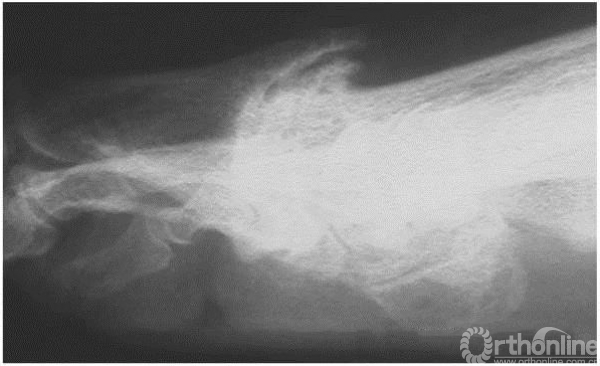

3期:侧位X线上,关节间隙变窄,累及超过1/4的关节间隙,背侧骨赘更为明显

4期:关节炎表现较3期更为明显、严重(3,4期影像学表现可以差别不大,但临床表现却相差很大)